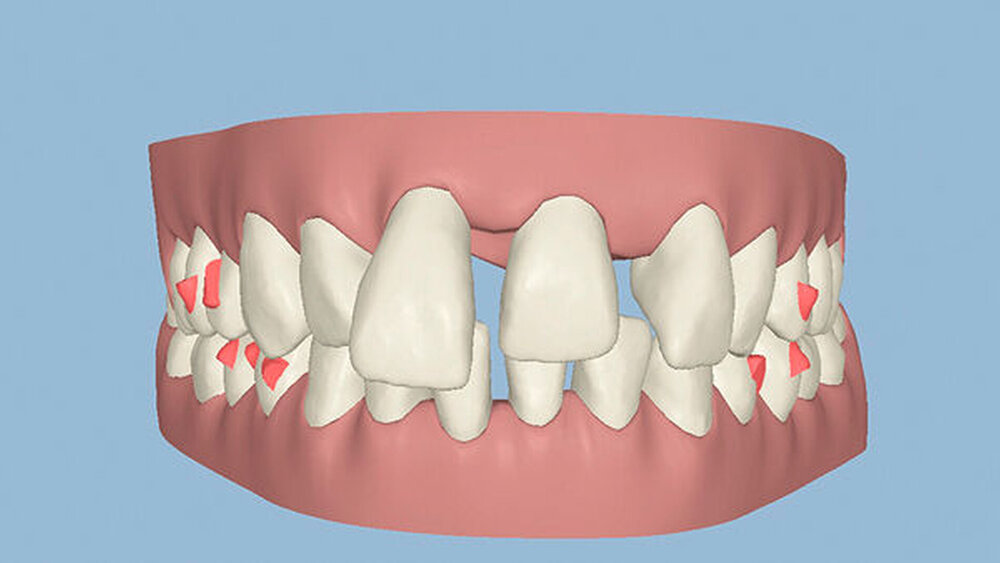

Kieferorthopädisch imponierte beidseits eine neutrale Verzahnung bei einem tiefen Biss von 5 mm – bedingt durch die Verlängerung beider Frontzahngruppen. Besonders Zahn 11 zeigte eine erhebliche Verlängerung und Protrusion mit einer sagittalen Frontzahnstufe von 5 mm. Sowohl die Frontzähne im Ober- als auch im Unterkiefer wiesen eine lückige Beziehung zueinander auf (Abbildung 1).